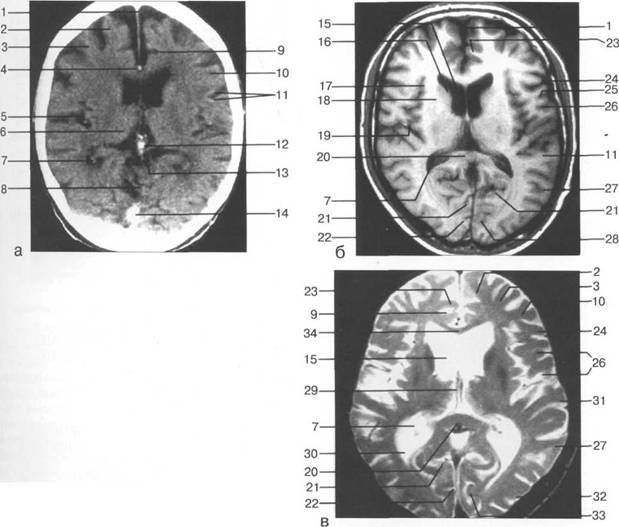

череп 13513u2010n 85;ой ямки, в некоторых случаях хорошо видны лентовидные уплотнения поперечного и III

мие; 26 - поясная борозда; 27 - головка хвостатого ядра; 28 - бледный шар; 29 - височный рог боково

цистерна четверохолмия; 14 -прямой синус; 15 -лобный рог; 16 - головка хвостатого ядра; 17 -перед